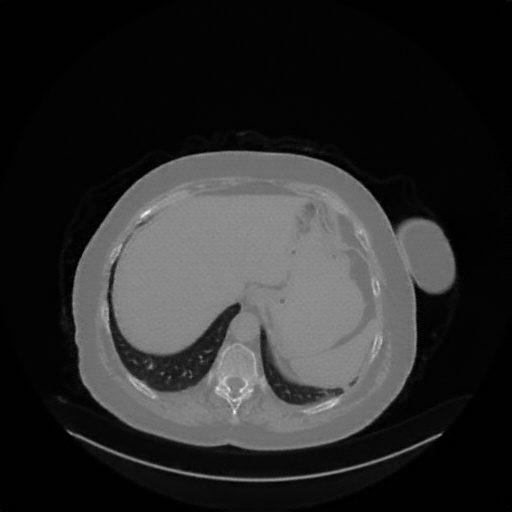

Image Grid

4Γ—3 grid: Rows show different image types (Original NATIVE, Reconstructed NATIVE, Original VENOUS, Generated VENOUS), Columns show windowing techniques (No Window, Lung Window, Mediastinum Window)

Generated VENOUS CT scan (A→B translation)

Full window (WL 1023.5, WW 4095 β†’ Low βˆ’1024, High +3071)